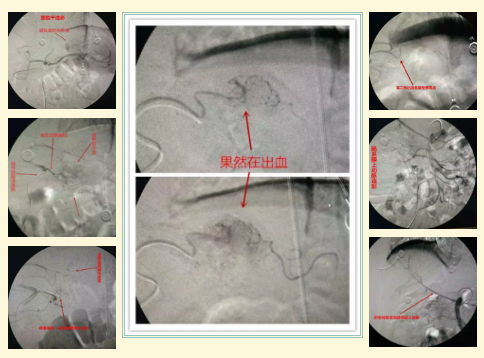

近日,我院放射科与西院区外科联合成功救治一名“胃恒径动脉综合症”致消化道出血患者,患者现已康复出院,恢复良好。

主管医师李新源立即与放射科主任唐小平联系沟通后,决定为患者行腹腔干+肠系膜上动脉+肠系膜下动脉造影寻找出血位置,必要时可行栓塞止血治疗。征得家属知情同意后,于入院第3日下午在放射科介入导管室为患者实施了腹腔干+肠系膜上动脉造影,造影时发现胃左动脉部分分支迂曲成团,可见造影剂外溢征象(只要出血>0.5ml/s造影时就会发现),随后行栓塞止血治疗,术程顺利,患者安返病房。

术后为患者停输止血药及收缩血管药物,并输悬浮红细胞3u+血浆600ml。术后第一日复查血常规提示:红细胞:2.76x 10^12/L,血红蛋白:80g/L,血小板:53 x 10^9/L。

后再未输血。术后第9天复查血常规提示:红细胞:3.01x 10^12/L,血红蛋白:94g/L,血小板:141 x 10^9/L。

消化道出血是消化系统病变常见的临床症状之一,血管造影对消化道出血的诊断和治疗非常有效。经导管内灌注血管收缩药物或栓塞治疗方法安全简便,疗效迅速可靠,往往能达到“立竿见影”的效果。